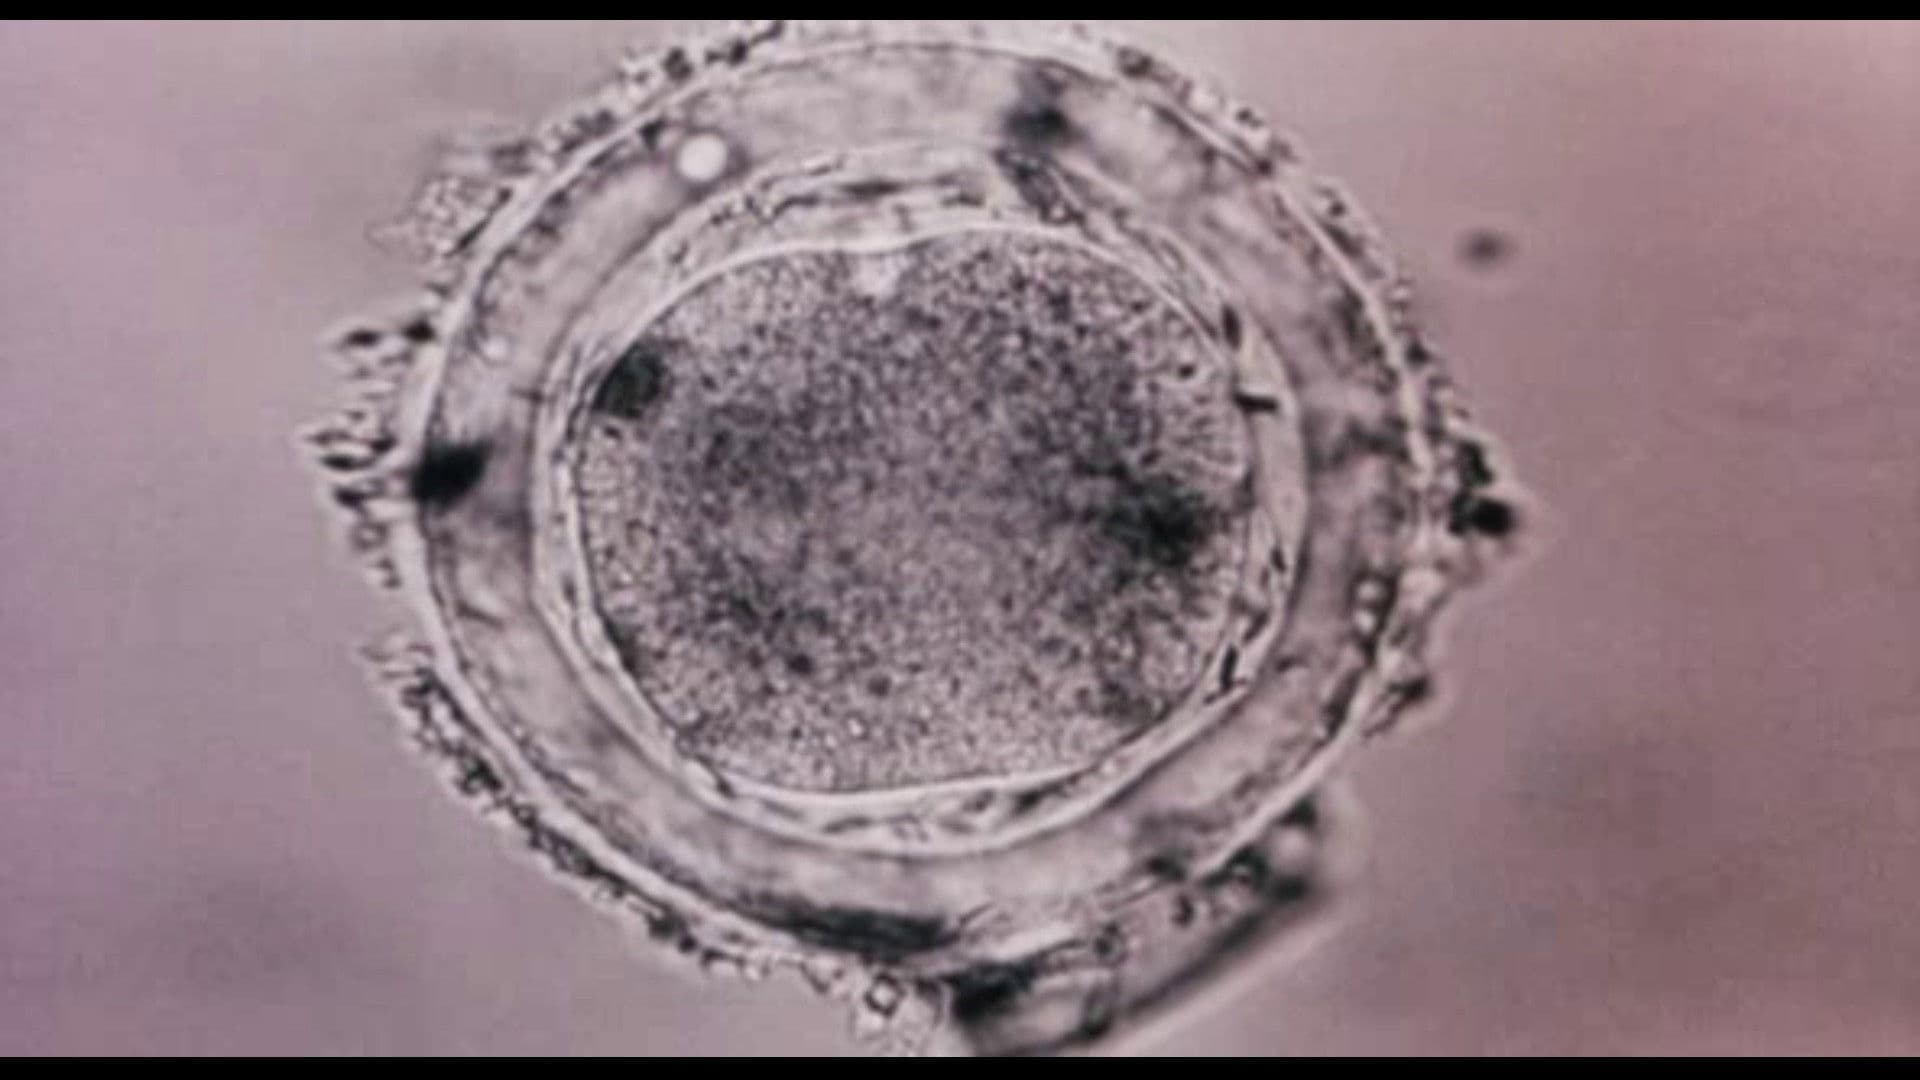

Bodysong

2003

83 min